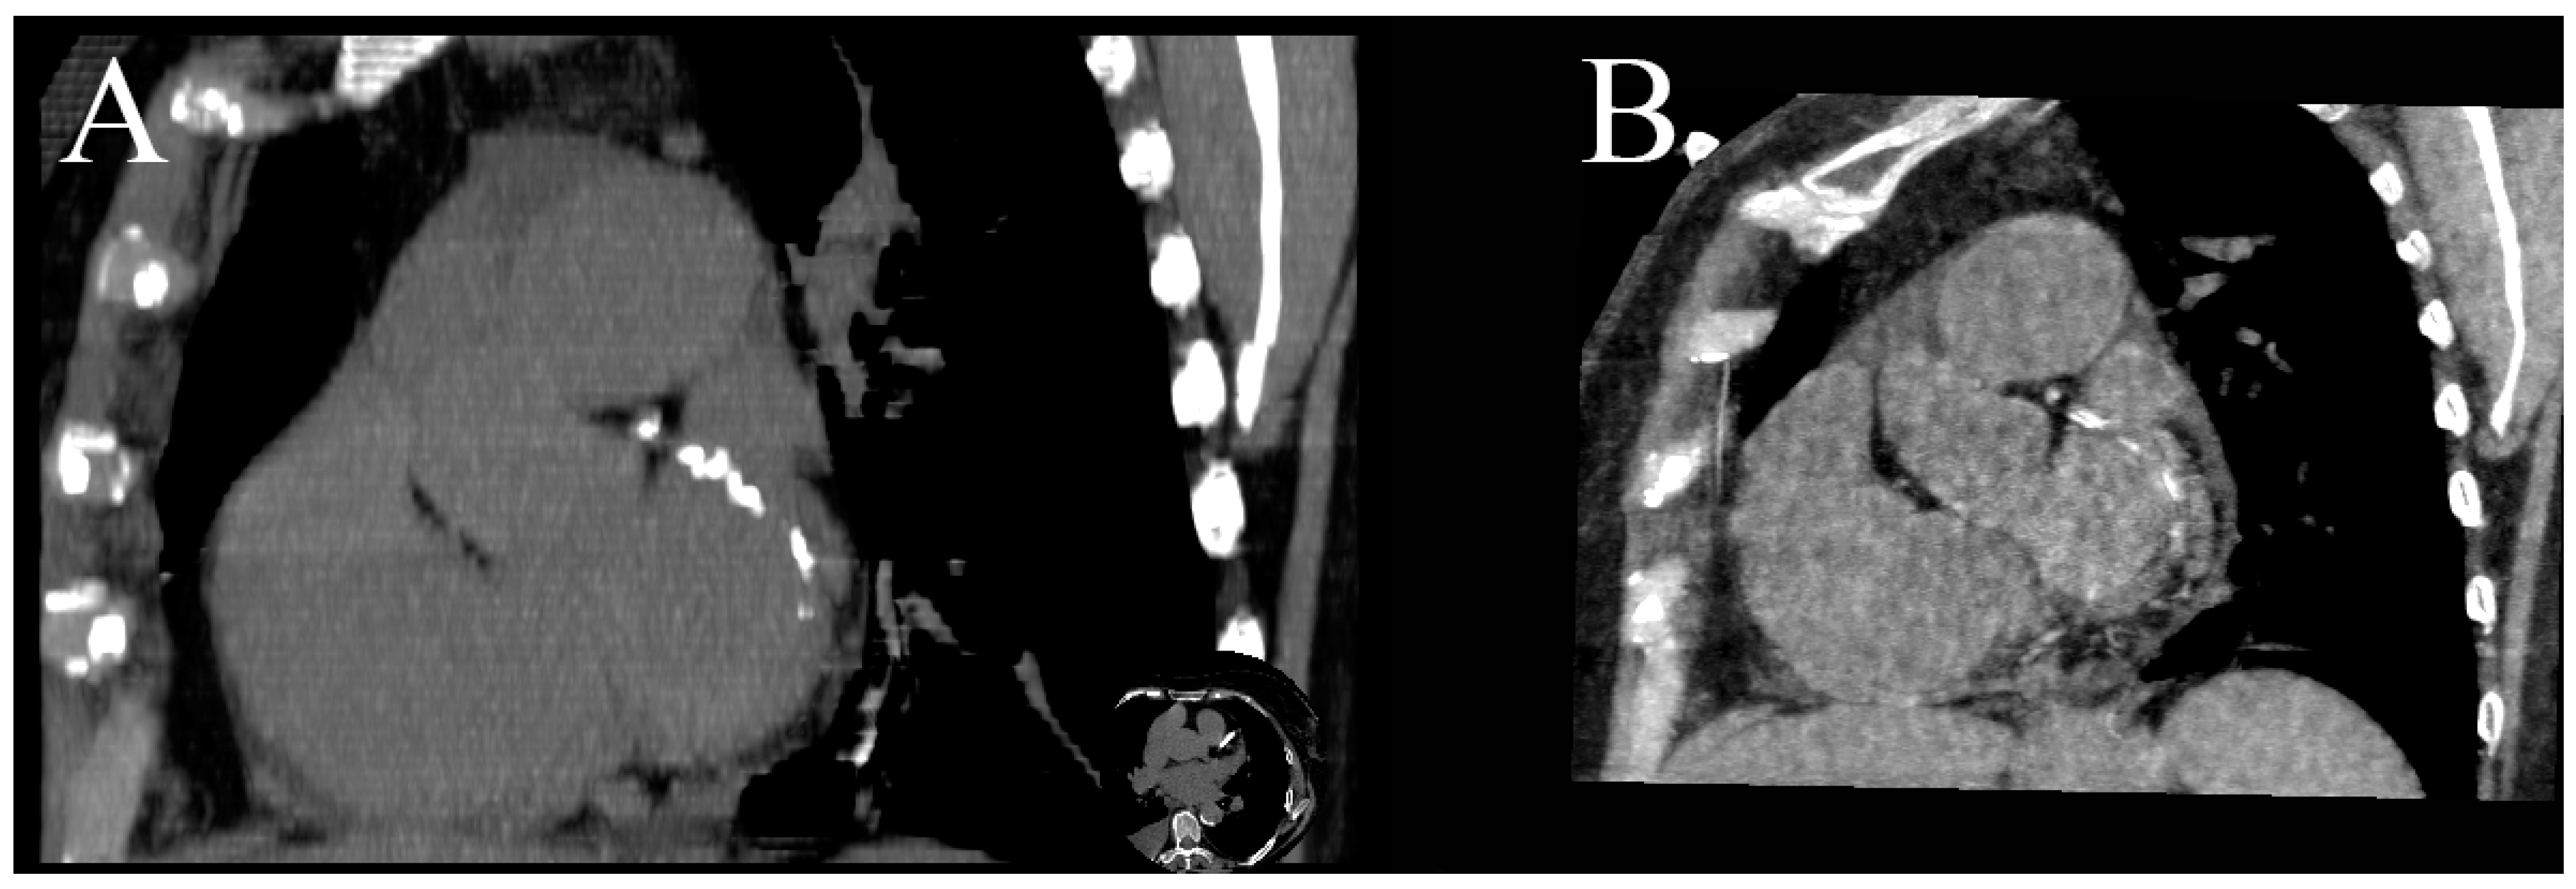

5.3. Radiation Dose Reduction

Coronary CTA originally had one the highest doses of radiation of all CT examinations; thanks to the development of prospective ECG-gating, current modulation and iterative reconstruction algorithms, it has been radically decreased, even to below 1 mSv [10]. It can be further reduced by omitting the noncontrast phase and using DECT’s capabilities of creating virtual unenhanced images (VUIs) [13,24]. Many phantoms and human-based experiments have proved that there is a strong correlation between the Agatston score calculated from the real unenhanced images and VUIs. However, none of the vendors that provide DECT scanners have FDA- or EU-approved Agatston scoring software for use with DECT contrast images [4,10,14,24,47]. In order to use calcium scoring from VUIs in routine clinical practice, precise software has to be modified, because it uses a threshold of 130 HU to extract calcium, whereas water (iodine) maps are coded in element concentrations, making automatic extraction impossible (Figure 5). Most vendors also offer a method of obtaining VUIs coded with Hounsfield units, but this method tends to misclassify small calcification as iodine and extract them as well.

Figure 5.

MPR MIP image of true unenhanced image (A) and water (iodine) map (B) showing calcifications in the LCx. The volume of calculated calcifications was 85 mL and 88 mL, respectively. Similar results, showing high correlation between calcium volume calculated from TUN and VUIs, were reported by [24].

The greatest dose reduction can be achieved using third-generation dual-source scanners capable of performing coronary CTA with pitch = 3 and a submillisievert radiation dose, but this mode can be used only in patients with low heart rates [10].